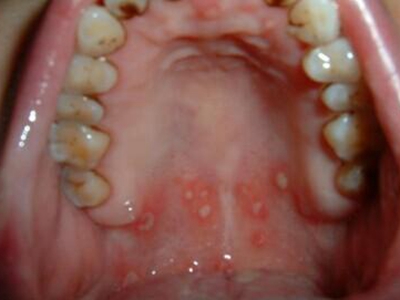

梅毒黏膜斑是二期梅毒最常见的口腔损害。可发生在口腔黏膜的任何部位,以唇黏膜最多见,其次为软腭、舌背、舌底等部位。损害呈灰白色、光亮而微隆的斑块,圆形或椭圆形,直径约1cm,边界清楚。易发生糜烂或浅表溃疡,表面覆盖灰白色假膜,周围有红晕。黏膜斑常为多个,内含有大量梅毒螺旋体。